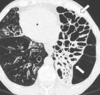

14

Q

A

Consolidación alveolar